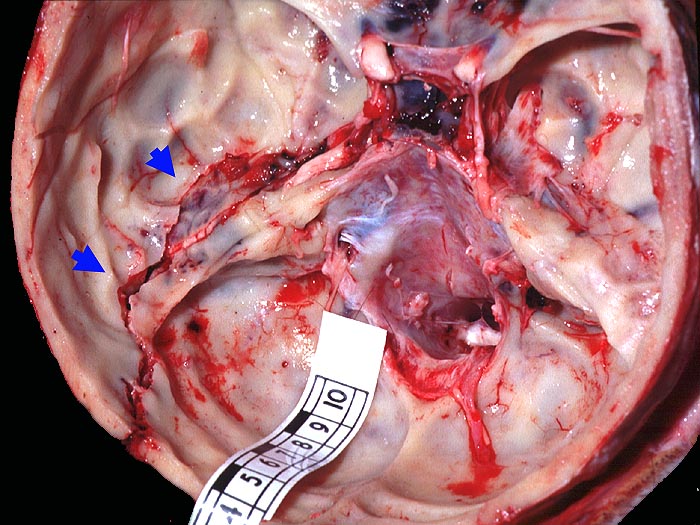

PathoPic – image database / PathoPic ID 1772 - Schädelbasisfraktur

Schädelbasisfraktur

Frische Schädelbasisfraktur im Bereich der vorderen Schädelgrube entlang dem Os ethmoidale, im Bereich der Pars petrosa des Os temporale sowie bis in den Bereich der hinteren Schädelgrube entlang der Sutura lambdoidea links reichend.

Frische kortiko-subkortikale Hirnkontusionen. Blutige Otorrhoe links. Herdförmige diffuse frische Subduralblutungen (ohne raumfordernde Wirkung). Monokelhämatom.

Verkehrsunfall.